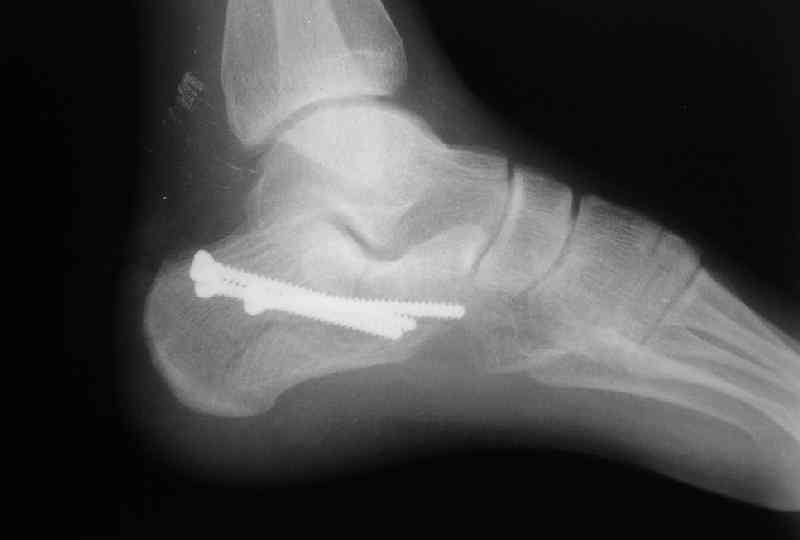

Re: Перелом пяточной кости

Открытый и закрытый способы лечения.